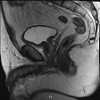

MRI of the pelvic organs.

МРТ органов малого таза. Современный неинвазивный метод диагностики, позволяющий получать трехмерные изображения органов малого таза путем регистрации радиоволн, излучаемых ядрами атомов водорода под воздействием магнитного поля. МРТ органов малого таза проводится как у женщин, так и у мужчин. У женщин исследуются матка, яичники, маточные трубы и влагалище, у мужчин - простата, семенный проток и семенные пузырьки, у обоих полов - нижняя часть мочеточника, мочевой пузырь, прямая кишка и мелкая тазовая ткань.